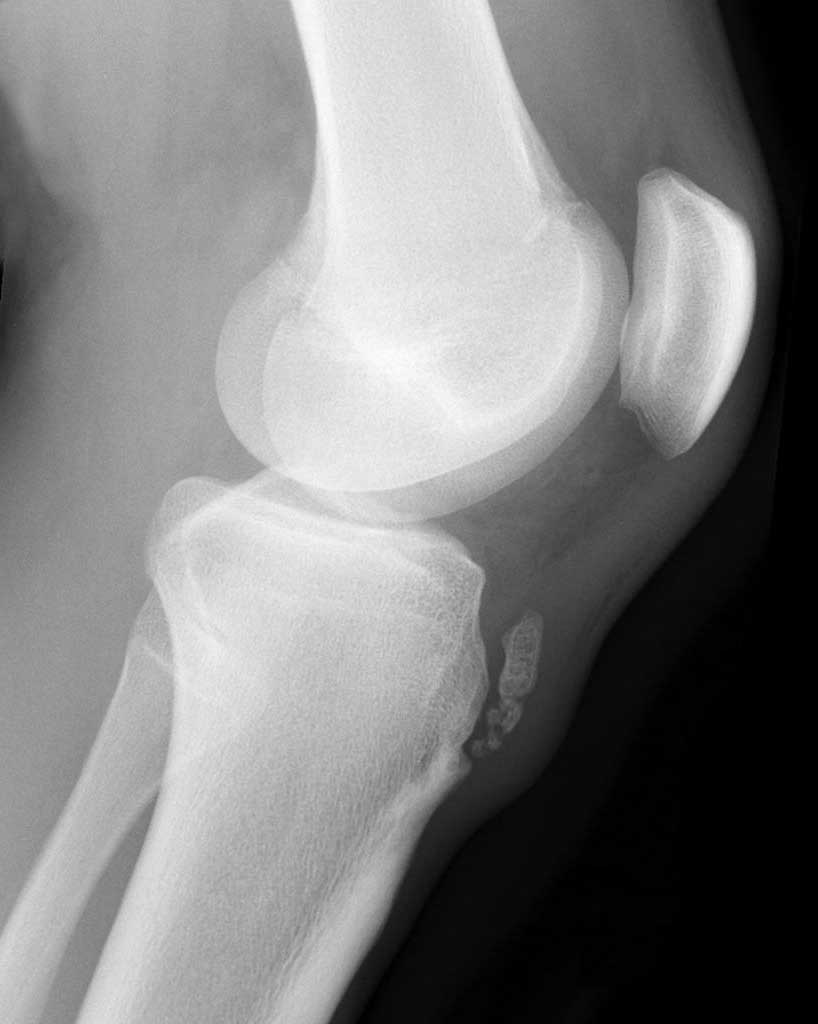

A doença de Osgood-Schlatter, embora tenha um nome complicado, é uma condição benigna que afeta adolescentes, sobretudo no surto de crescimento, tendo como principal sintoma a dor abaixo do joelho, após atividade física. O que é a doença de Osgood-Schlatter, como é feito seu diagnóstico e o tratamento? É sobre esses temas que falaremos hoje, confira!. Entre as lesões que ocorrem na prática de esportiva por crianças temos a patologia/síndrome de Osgood-Schlatter que foi primeiramente descrita em 1903 por Osgood, e surge durante a adolescência em forma de tumefação em torno do tubérculo tibial e do tendão patelar (LOVELL e WINTER, 1988). Ou seja, é uma condição comum que ocorre a.

A doença de Osgood-Schlatter é uma inflamação dolorosa do osso e da cartilagem na parte superior da tíbia (osso da canela). Em geral, a doença de Osgood-Schlatter se desenvolve em crianças entre 10 e 15 anos de idade que praticam esportes. É causada por uso excessivo da perna.. A doença de Osgood Schlatter é uma osteocondrose, uma condição temporária que pode causar dor e inchaço nos joelhos, sendo um dos problemas musculoesqueléticos mais comuns em crianças, adolescentes e atletas em fase de crescimento. A doença se manifesta em grande parte em apenas um dos joelhos, entre os 10 e 15 anos de idade e na sua.